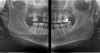

Figure 3  Example of a pan bitewing.

Figure 3